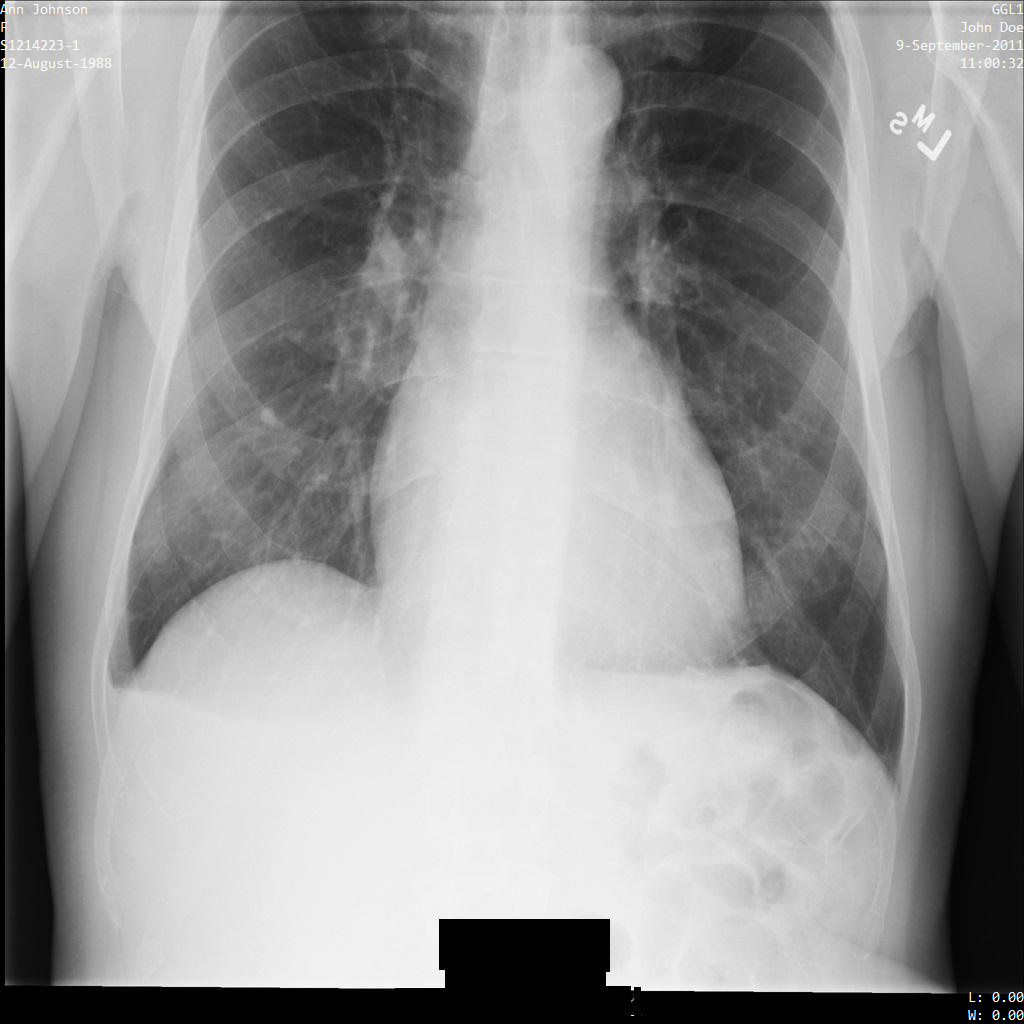

以下各節提供範例,說明如何使用各種方法去識別 DICOM 資料。每個樣本都會提供去識別化圖片的輸出內容。每個範例都會使用下列原始圖片做為輸入內容:

您可以比較各項去識別化作業的輸出圖片與原始圖片,瞭解作業效果。

將圖片提交給 Cloud Healthcare API 後,圖片會如下所示。雖然圖片頂端角落顯示的中繼資料已遭塗銷,但圖片底部的內建受保護健康資訊 (PHI) 仍存在。如要一併移除內建文字,請參閱「從圖片中遮蓋內建文字」。